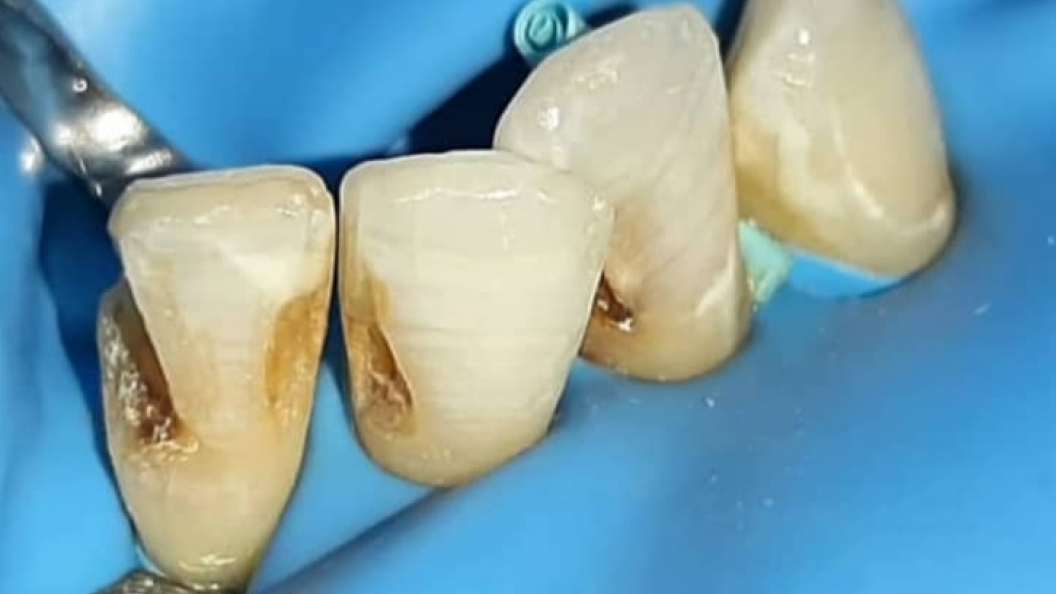

В «Стоматологию комфорта» обратилась пациентка с жалобами на эстетические дефекты 3.2, 3.1, 4.1 зубов. В процессе осмотра врач Серебрякова Мария Борисовна диагностировала хронический средний кариес зубов. Врач сделала заключение о целесообразности лечения и реставрации зуба при помощи композита Estelite.

В ходе лечения проведены следующие работы:

- введение анестетика;

- применение системы коффердам;

- механическая обработка кариозной полостей;

- медикаментозная обработка;

- наложение лечебной прокладки;

- наложение изолирующей прокладки;

- пломбирование композитом Estelite;

- шлифовка и полировка пломбы;

- обработка полости рта.